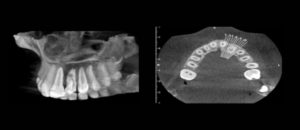

192 – Clasificación propuesta para los contactos interproximales de los molares primarios utilizando CBCT: Un estudio piloto

El «Área de contacto» es un término que se usa para denotar las alturas proximales del contorno de las superficies mesial y distal del diente.